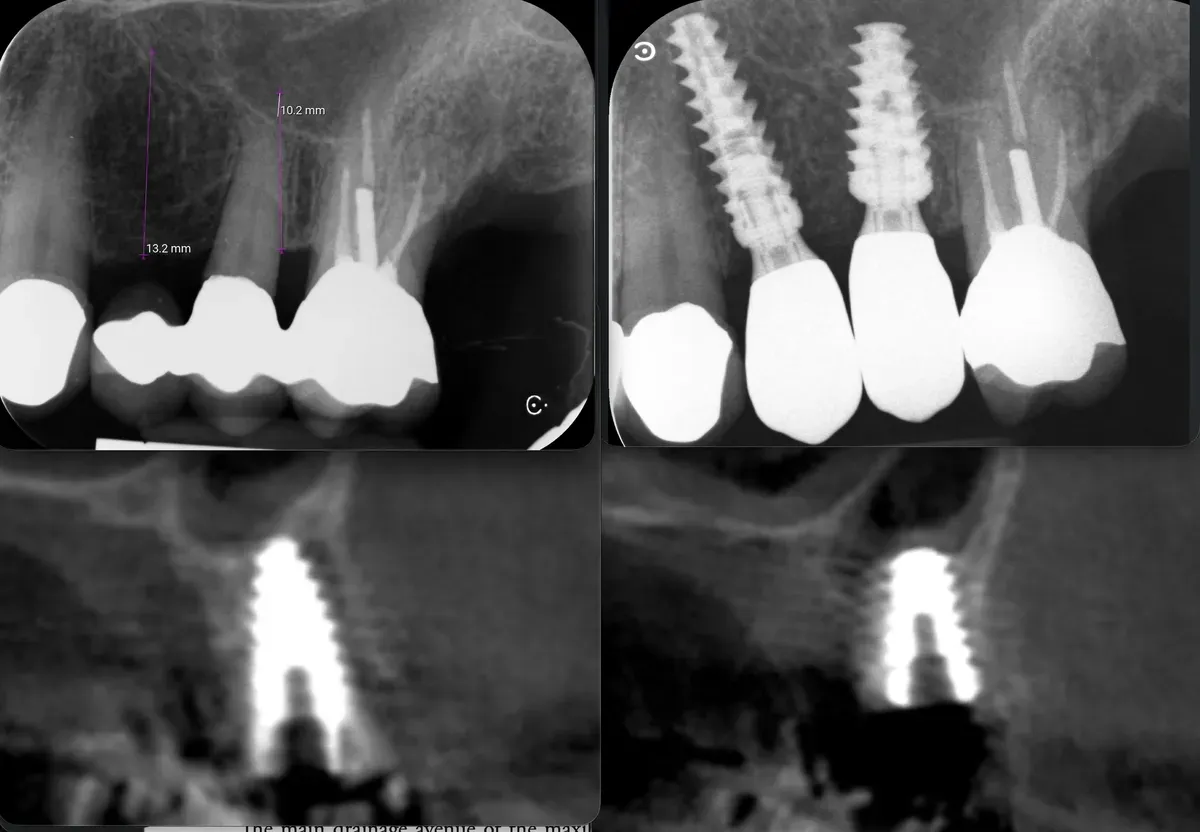

Con gli espansori da 13mm in posizione ho effettuato un controllo radiografico della posizione, prima di procedere ulteriormente.

Strumenti espansori da 13mm in posizione

La CBCT intraoperatoria ha confermato la corretta posizione tridimensionale degli espansori e il raggiungimento della corticale del pavimento del seno in zona 2.5. In caso di dubbi sulla posizione e nel corso di interventi delicati come questo, questo ausilio strumentale è di fondamentale importanza. Ma non è sempre necessaria. L’esposizione, per quanto contenuta, dev’essere sempre ridotta al minimo, compatibilmente con la sicurezza chirurgica.

Visione laterale espansori

Sezione espansore sito 2.4

Sezione espansore sito 2.5